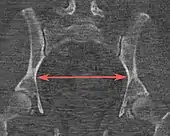

| Pelvic inlet | Transverse diameter of the pelvic inlet | ![]() |

![]() Coronal plane |

The iliopectineal lines, at widest transverse distance. | 13 to 14.5 cm.[4] |